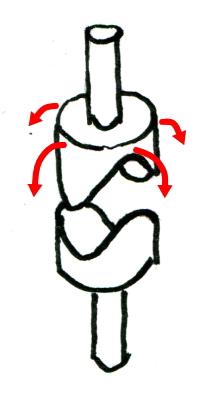

鞍関節

| 馬の鞍(くら)を上下に重ねたような形から鞍関節(あんかんせつ)。楕円関節同様回旋は出来ない2軸の関節。母指の手根中指節関節。 |